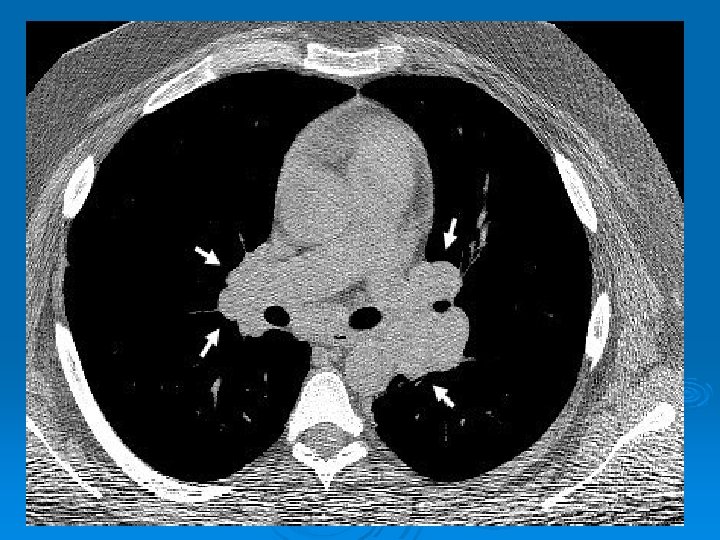

HRCT Ø Akciğer grafisine göre daha duyarlı Ø Paratrakeal, pretrakeal, paraaortik ve subkarinal adenopatilerde tespit edilebilir